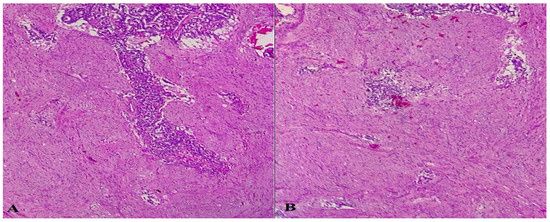

4. Case Report 3

5. Discussions and Literature Review